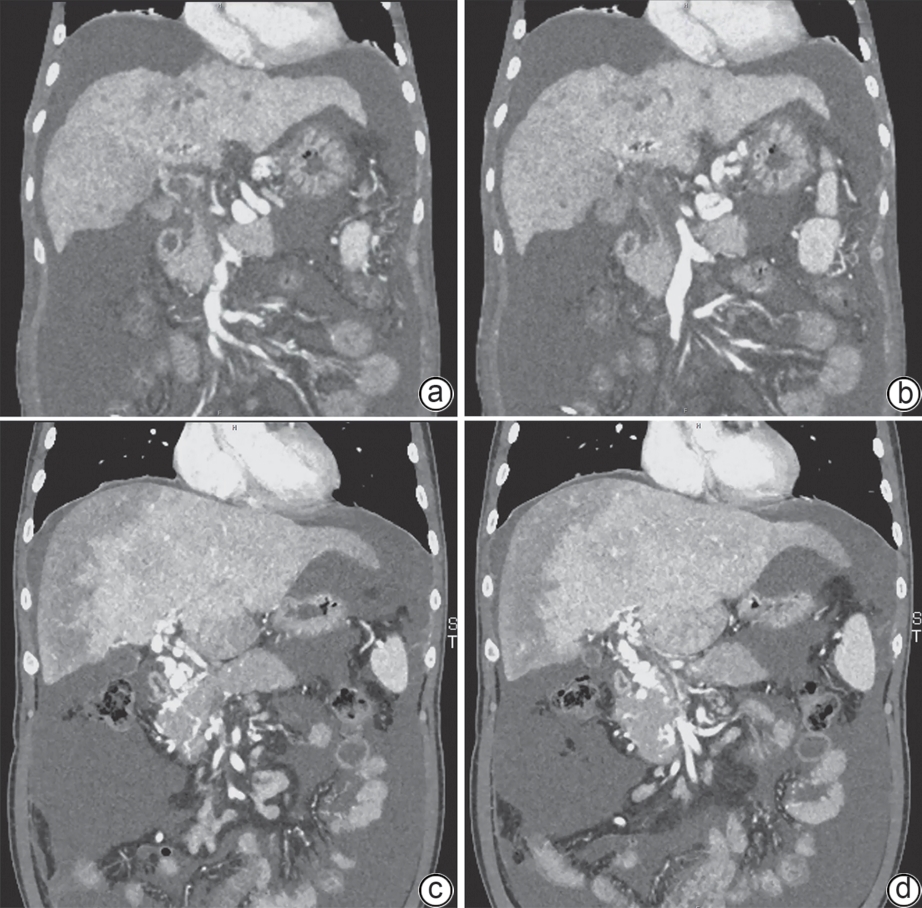

胸腺素β4对四氯化碳诱导的肝纤维化小鼠模型的影响及其作用机制

朱耘函, 王思琪, 景登娅, 冯勤颖

2026, 42(3): 593-599. DOI: 10.12449/JCH260314

摘要:

目的  本研究拟探讨胸腺素β4(Tβ4)通过调控血小板衍生生长因子(PDGF)表达及诱导肝星状细胞(HSC)凋亡,对四氯化碳(CCl4)诱导的肝纤维化小鼠模型的干预作用与潜在机制,为临床抗肝纤维化治疗提供新的实验依据。  方法  选取30只雄性C57小鼠,随机分为正常对照组、模型组,以及Tβ4低(3 mg/kg)、中(6 mg/kg)和高(12 mg/kg)剂量治疗组,每组6只。正常对照组自由摄食普通饲料,其余各组腹腔注射50% CCl4与橄榄油混合液建立肝纤维化模型,经超声及病理学验证造模成功后,对各治疗组小鼠连续皮下注射Tβ4干预4周。实验结束后取肝组织行苏木精-伊红及Masson染色观察组织病理变化,应用实时荧光定量聚合酶链反应检测血PDGF mRNA表达,原位末端转移酶标记(TUNEL)法检测HSC凋亡情况。计量资料多组间比较采用单因素方差分析,进一步两两比较采用LSD-t检验。  结果  与模型组比较,Tβ4中、高剂量治疗组小鼠肝纤维化程度均呈现不同程度的减轻。实时荧光定量聚合酶链反应结果显示,Tβ4可显著下调肝组织中PDGF mRNA表达,各剂量治疗组间差异有统计学意义(P<0.05);Tβ4高剂量组与正常对照组PDGF mRNA表达差异无统计学意义(P<0.05)。TUNEL检测结果显示,Tβ4中、高剂量组HSC凋亡数量显著多于模型组。  结论  Tβ4可能通过抑制PDGF表达和促进HSC凋亡,从而改善CCl4诱导的小鼠肝纤维化,提示其在肝纤维化治疗中具有潜在应用价值。